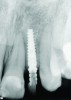

Fig 6. Radiograph of crown Nos. 8 and 9, 2 years after implant placement.

Figure 6